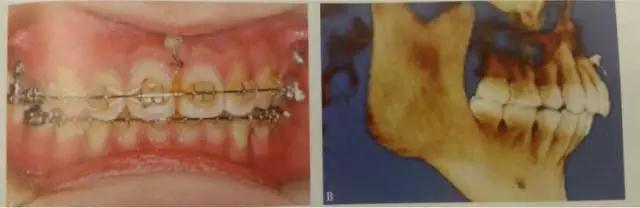

這是臨床上常見(jiàn)的應(yīng)用方式,多用于需要強(qiáng)支抗內(nèi)收前牙,常種植于第二前磨牙與第一磨牙、第一磨牙與第二磨牙之間,應(yīng)根據(jù)X線片觀察牙根間距離和鄰近解剖結(jié)構(gòu)確定具體部位,采用微種植體一方面可以獲得支抗以盡可能內(nèi)收前牙,另一方面可整體內(nèi)收6個(gè)前牙而不擔(dān)心支抗問(wèn)題,節(jié)省了調(diào)節(jié)時(shí)間。

頰側(cè)可以植于第二前磨牙和第一磨牙牙根間,第一磨牙頰側(cè)近遠(yuǎn)中根、或第一磨牙和第二磨牙根尖之間。對(duì)于有些上頜合平面偏斜、單側(cè)后牙鎖結(jié)、個(gè)別后牙因?qū)涎廊笔Ф扉L(zhǎng)等患者,可以考慮單側(cè)后牙區(qū)植入微種植體。對(duì)于前牙開(kāi)合畸形,下頜缺乏縱合曲線,spee曲線過(guò)于平坦,雙側(cè)后牙正鎖合等情況。